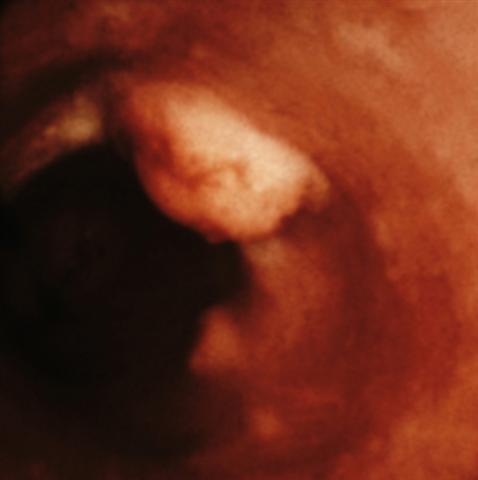

Рис. 13. Эндоскопическая картина лейомиомы пищевода.